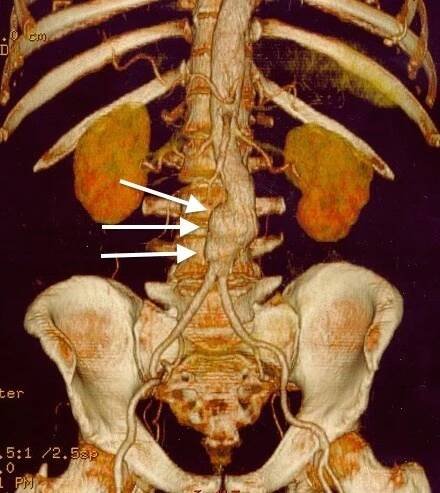

3D rekonstrukce CT skenu aneuryzmatu břišní aorty.